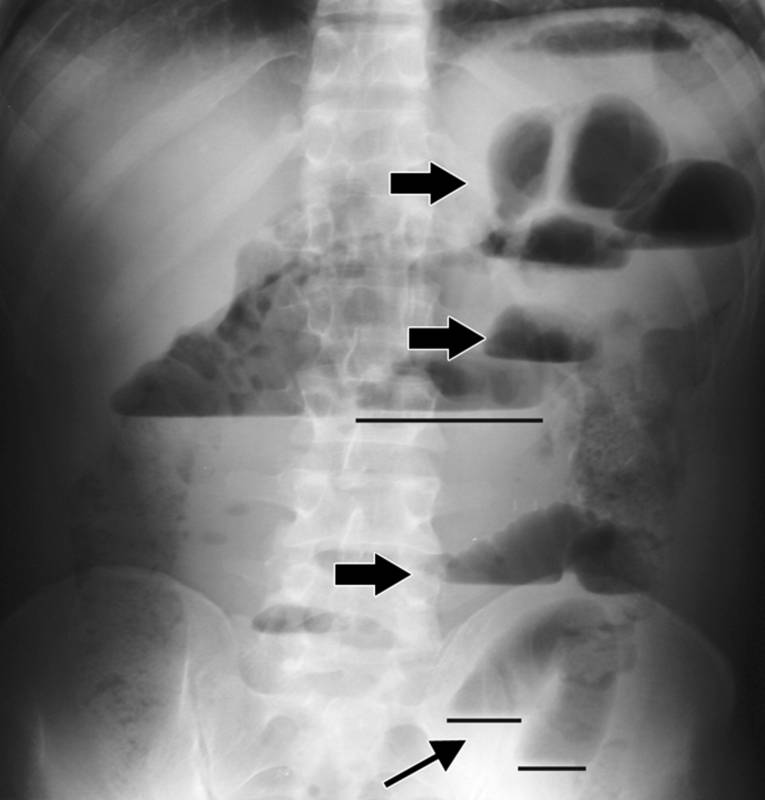

- обзорная рентгеноскопия и -графия органов брюшной полости – во время нее определяют, что петли кишечника значительно раздуты (так называемая пневматизация кишечника), а в брюшной полости имеется жидкость (выпот, который в данном случае образуется вследствие развития перитонита);